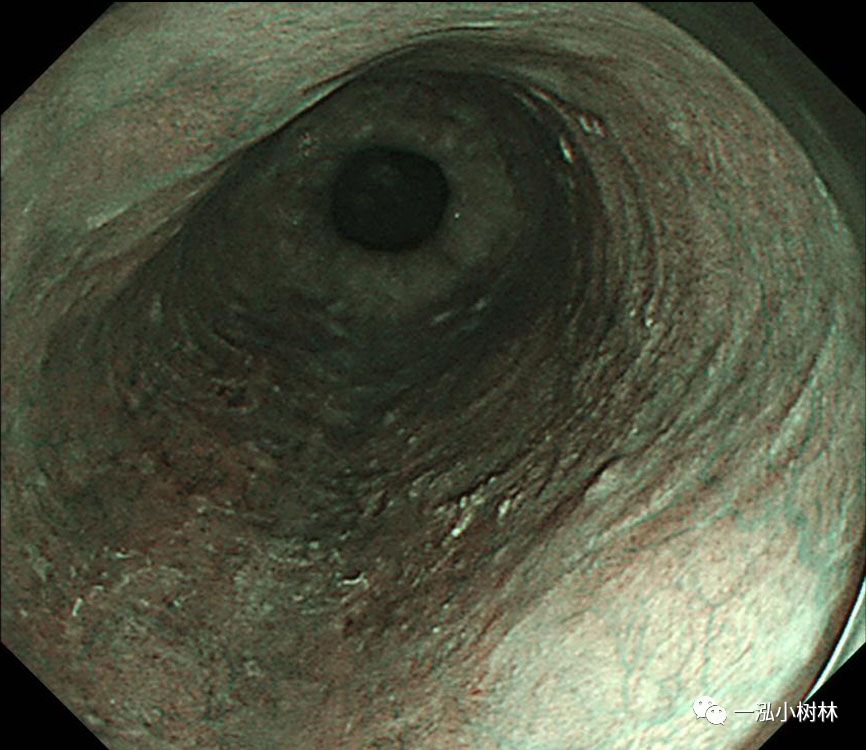

图2 NBI:病变呈褐色(BA)